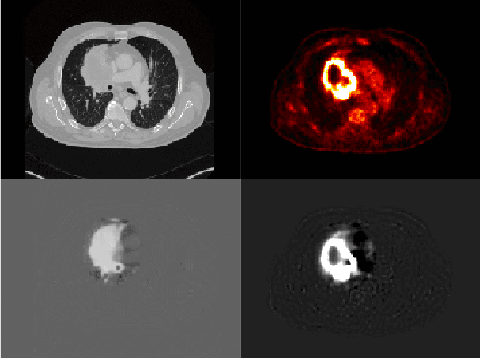

Abstract:Tumor segmentation in PET-CT images is challenging due to the dual nature of the acquired information: low metabolic information in CT and low spatial resolution in PET. U-Net architecture is the most common and widely recognized approach when developing a fully automatic image segmentation method in the medical field. We proposed a two-step approach, aiming to refine and improve the segmentation performances of tumoral lesions in PET-CT. The first step generates a prior tumor appearance map from the PET-CT volumes, regarded as prior tumor information. The second step, consisting of a standard U-Net, receives the prior tumor appearance map and PET-CT images to generate the lesion mask. We evaluated the method on the 1014 cases available for the AutoPET 2022 challenge, and the results showed an average Dice score of 0.701 on the positive cases.